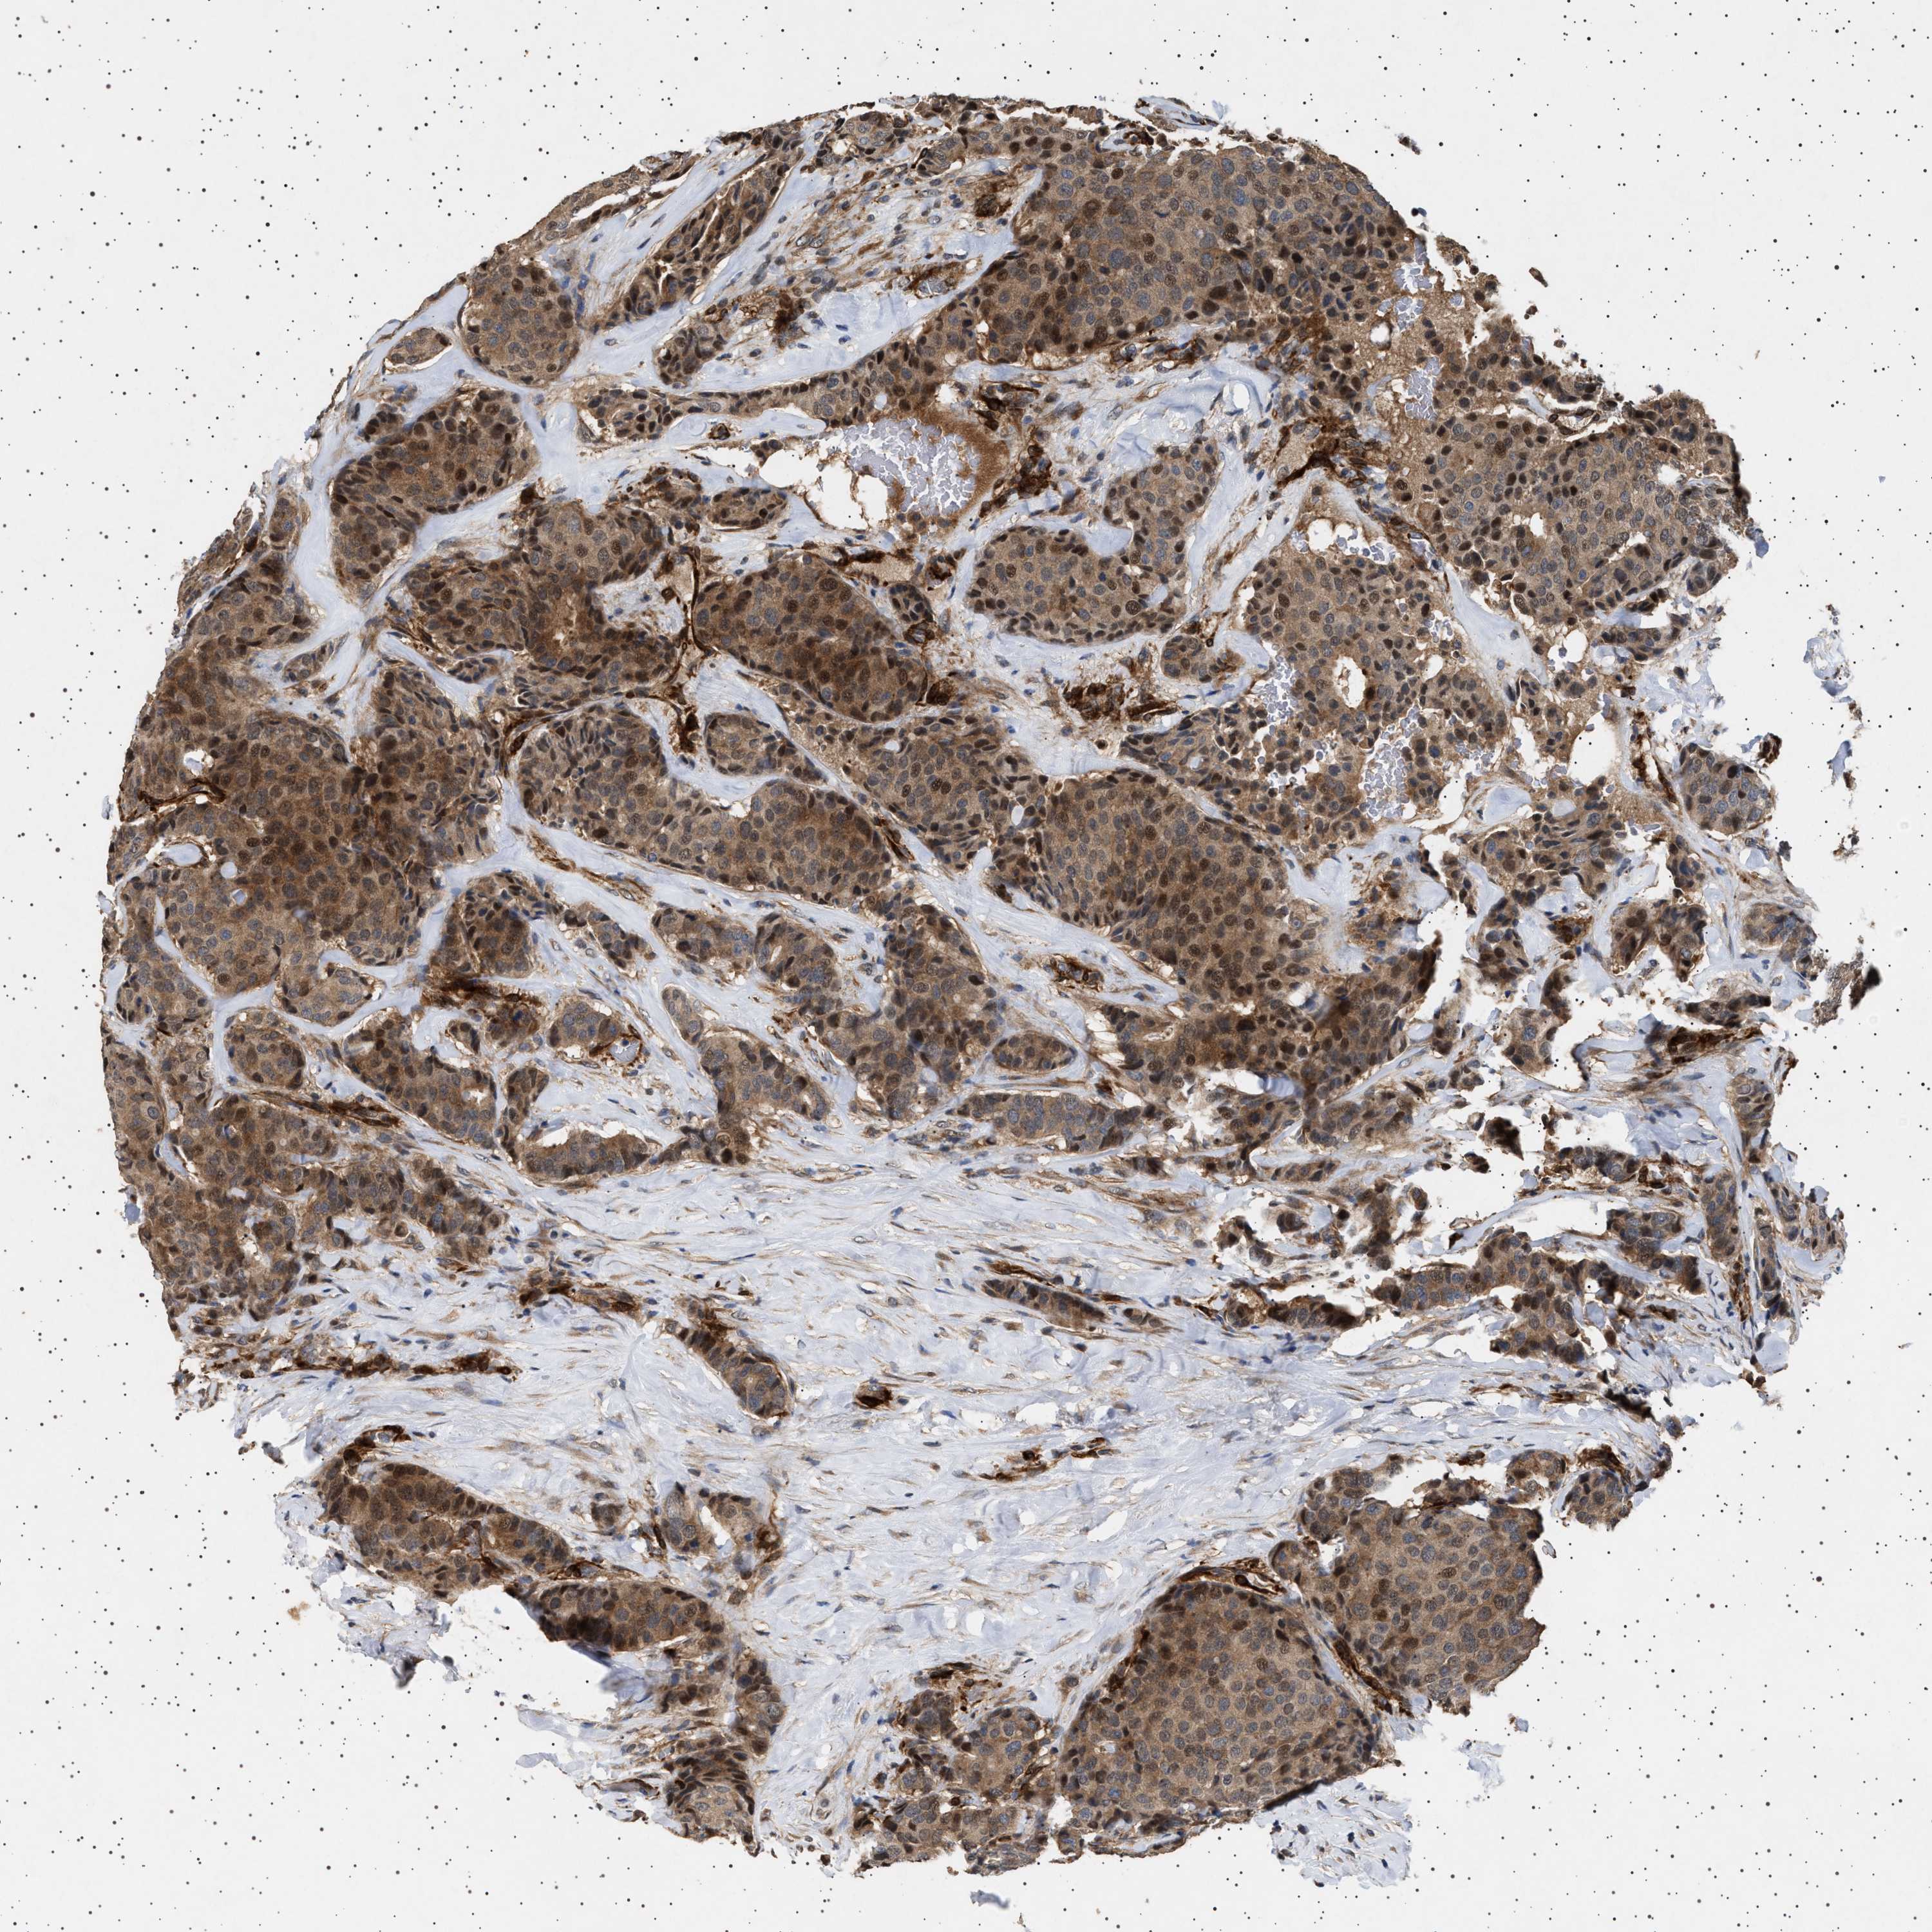

BRCA TCGA BRCA VALIDATION PROTEIN EXPRESSION